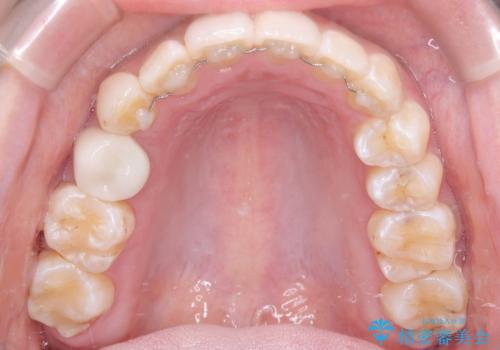

「フルリンガル矯正|アンカースクリューを活用し正中を整えた症例」

- 治療計画

矯正装置を装着し、アンカースクリューを活用しながら奥歯を少しずつ後ろへ動かし、正中を整えていきました。治療には時間がかかりましたが、計画通りに歯を移動させ、バランスの取れた歯並びへと仕上げることができました。裏側矯正のため、見た目を気にすることなく治療を進められた点も、患者様にとって大きなメリットでした。治療後は、「正中がしっかり合って、口元がスッキリした」とご満足いただきました。